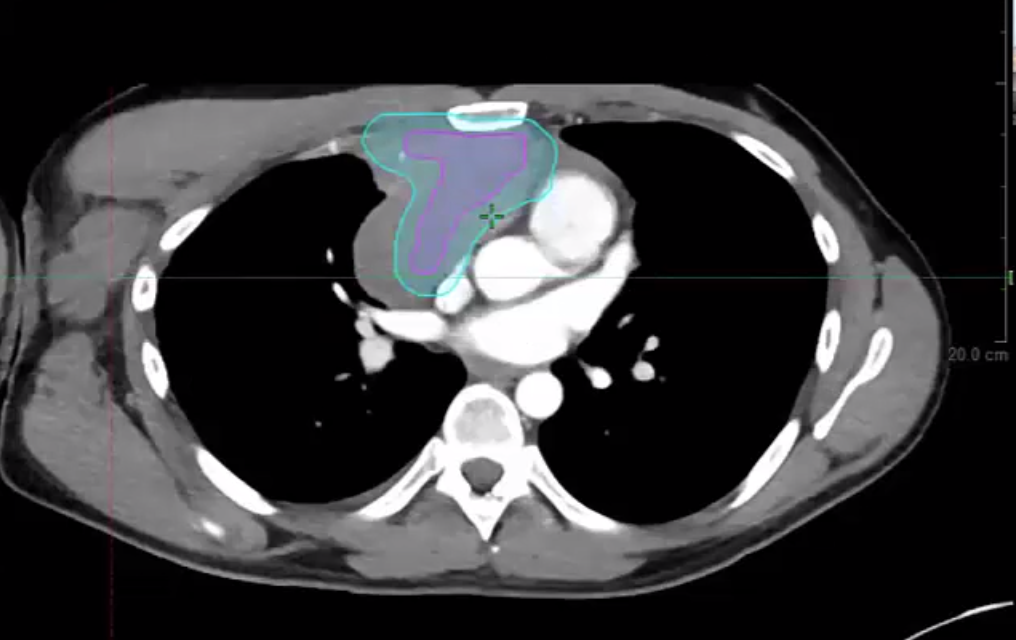

04/21/21 - Dr. Andrea Ng - Radiation Oncology - Lymphoma

05/12/21 - Dr. Andrea Ng - Radiation Oncology - Lymphoma

Lymphoma radiation, dose, local palliation, CTV